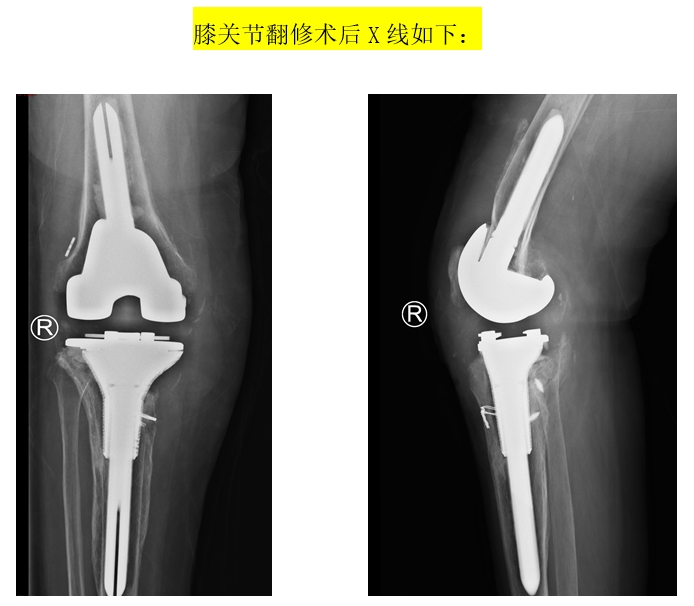

患者74岁女性,8年前在外院进行“右膝人工关节置换术”,6年前出现发热症状,右膝关节伤口部位有肿块,药物治疗后症状减轻但又多次复发,4个月前来到我院进行“右膝关节假体取出,清创,旷置术”,感染控制后进行“右膝人工关节翻修术”。患者入院后,谭红略主任组织专家针对此患者手术进行讨论,考虑患者经济情况较差,且胫骨内侧缺损较多,手术复杂、难度大,风险较高,一致认为目前常规的关节翻修假体已难以满足患者目前复杂的病情,需要寻找一种更加精准、个体化的治疗方案。在对患者病情进行深入分析后,手术团队决定采用个体化3D打印技术,制定个体化的关节翻修假体及相关手术方案。

高孔隙率多孔结构金属材料具有优良的骨整合性能,为股骨、胫骨的节段骨缺损或巨大的中央型骨缺损(AORI II和III型)修复提供了新的解决方法。采用这种结构的填充物可以在修复骨缺损的同时为关节假体提供长久可靠的结构支撑。利用不同型号和形态的金属补块可以很好应对干骺端骨缺损问题,尤其是那些仍残留有部分皮质骨的巨大中央型缺损。通过对骨床的修整可以增大金属补块与宿主骨的接触,提高稳定性。两者间的缝隙可以用颗粒骨填充,以修复骨量。金属补块与关节假体间可通过骨水泥或锥锁进行固定,提供假体稳定性。

运用3D打印技术进行膝关节翻修手术具有重要的意义,根据患者的具体病情,通过对膝关节的CT扫描数据进行处理,可以精确地打印出与骨骼结构完全匹配的膝关节假体,提高手术的精度和成功率,减少手术风险和并发症。个体化定制的假体可以更好地适应患者的身体,为精准医疗提供了有力的支持。